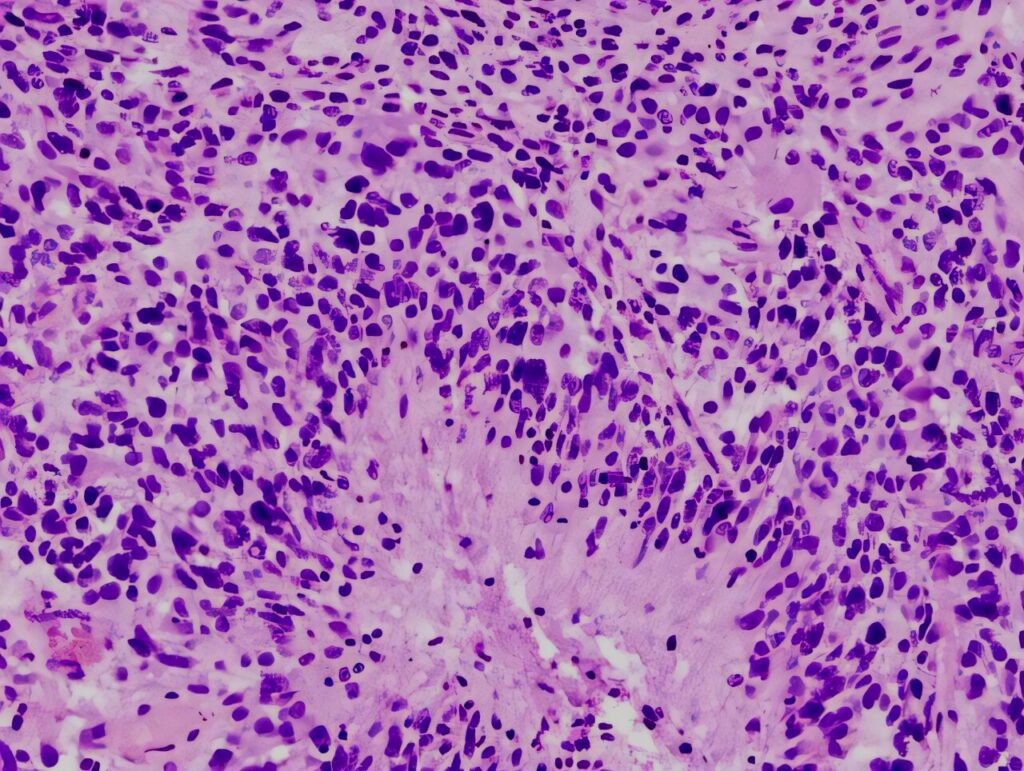

In neuro-oncology, understanding the biology of a brain or spinal tumor is essential for selecting the most effective and individualized treatment plan. Diagnostic tools such as biopsy, histology, immunohistochemistry, and molecular testing are required to accurately classify...